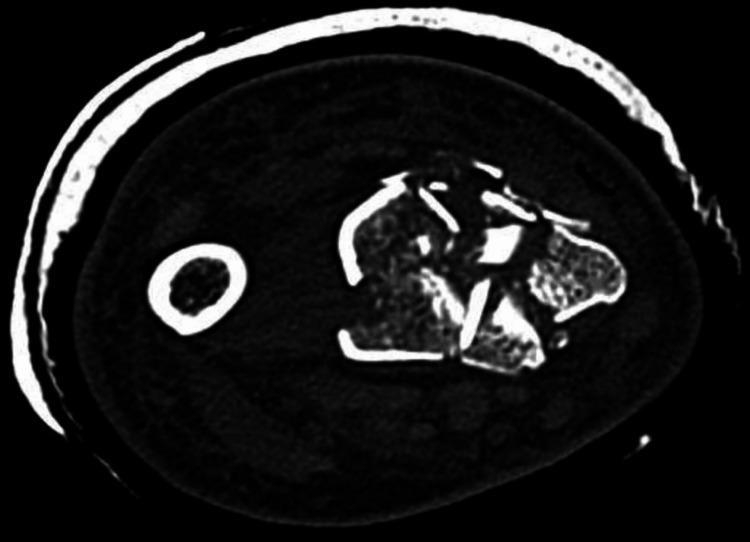

The most prevalent long bone fracture is that of the distal radius, and it affects all age groups. These fractures can present after low-energy or high-energy trauma, and their configuration often varies depending on the mechanism of injury. Their management can be operative or non-operative, and the scientific literature is abundant in studies comparing these two treatment modalities. There is also a healthy scientific debate as to the indications that should guide surgery for these injuries. A male patient sustained a high-energy fracture to his distal radius and presented to our unit soon after the injury. His fracture presented significant surgical challenges due to its complexity. It was stabilised surgically, and the patient recovered good function after rehabilitation. This case aims to demonstrate a surgical treatment protocol and the relevant surgical considerations when dealing with significant injuries, such as the one presented in this paper, where traditional fixation techniques may not yield a satisfactory outcome.

最常见的长骨骨折是桡骨远端骨折,它影响所有年龄组。这些骨折可在低能量或高能量创伤后出现,其形态通常因损伤机制而异。其治疗方法可以是手术治疗或非手术治疗,科学文献中有大量比较这两种治疗方式的研究。对于指导这些损伤手术治疗的适应症也存在健康的科学争论。一名男性患者桡骨远端遭受高能量骨折,受伤后不久就诊于我们科室。由于其复杂性,他的骨折带来了重大的手术挑战。通过手术使其稳定,患者康复后功能恢复良好。本病例旨在展示一种手术治疗方案以及处理重大损伤时的相关手术注意事项,比如本文所呈现的这种损伤,传统固定技术可能无法取得满意的效果。